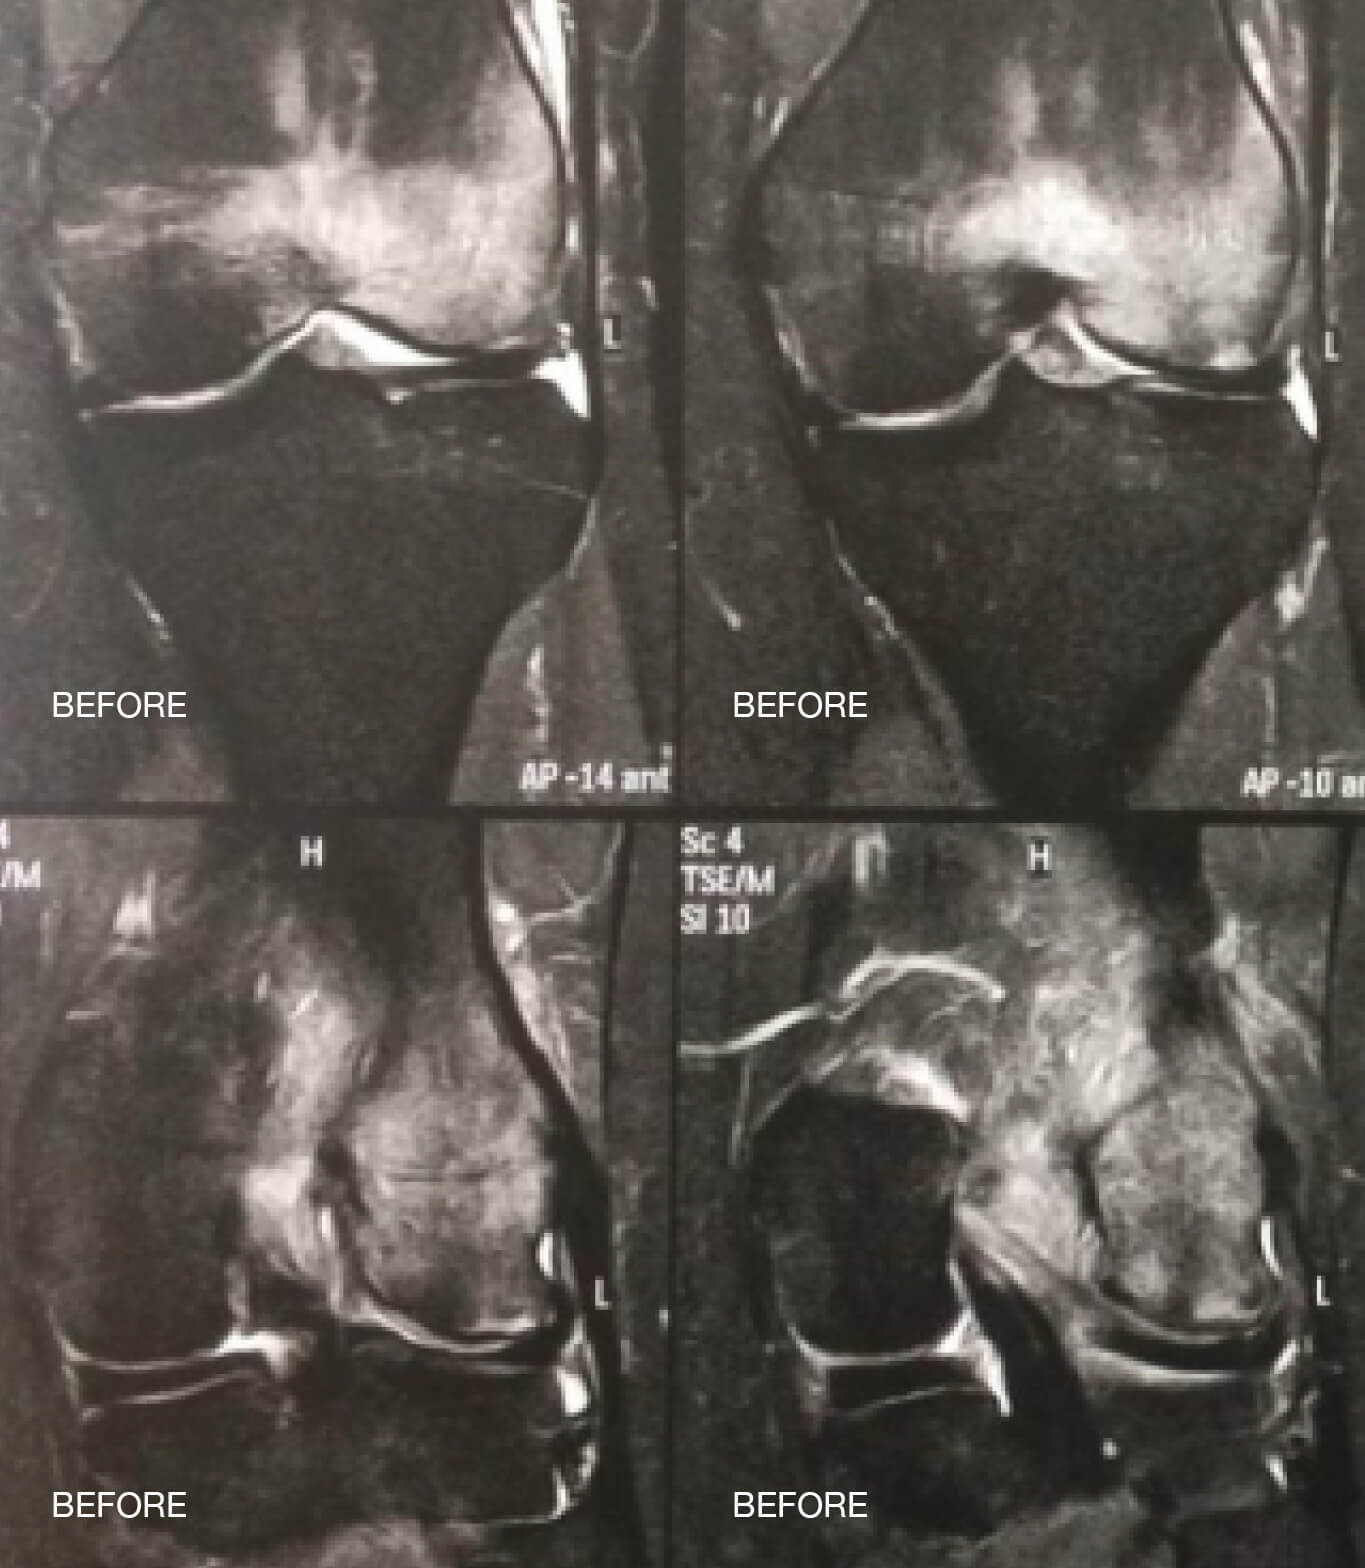

Οι ακόλουθες εικόνες απεικονίζουν ένα οίδημα μυελού των οστών στην άρθρωση του γόνατος πριν και μετά τη θεραπεία papimi. Η θεραπεία ήταν επιτυχής μετά από μόλις 10 συνεδρίες.

Πριν από το